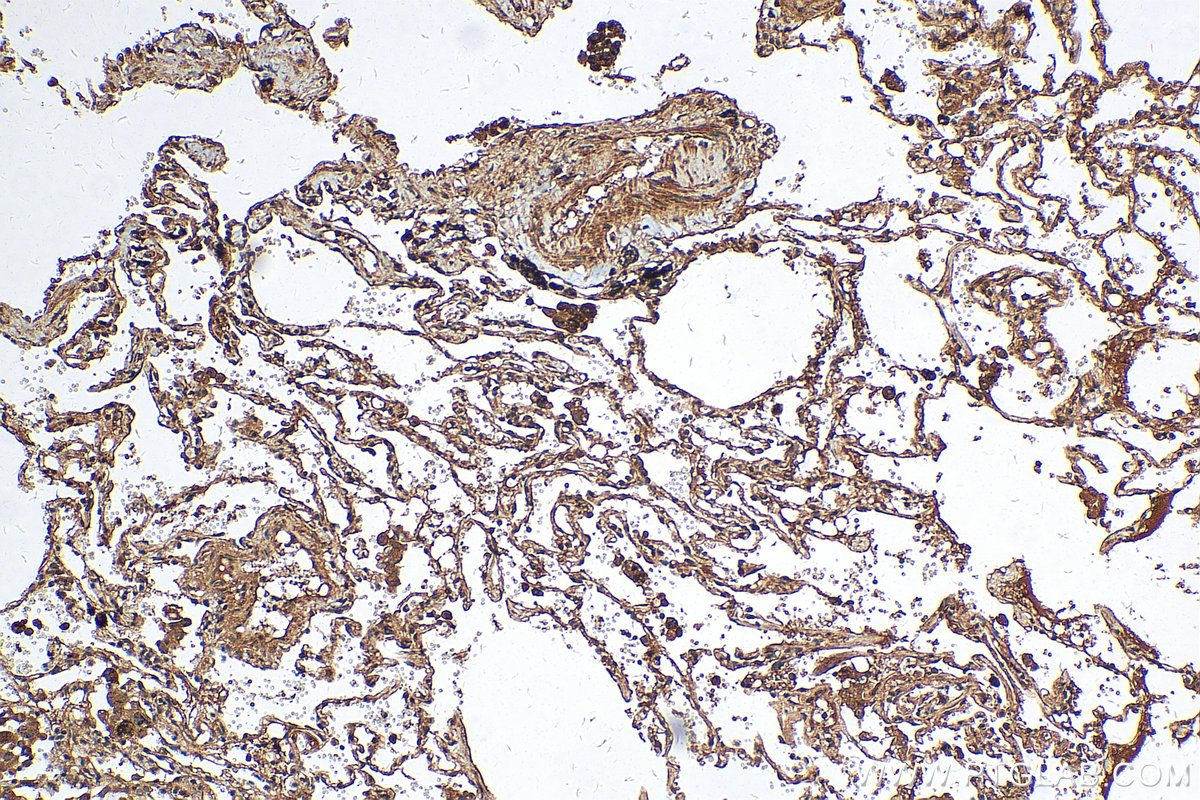

| Positive IHC detected in | human lung cancer tissue, human colon cancer tissue Note: suggested antigen retrieval with TE buffer pH 9.0; (*) Alternatively, antigen retrieval may be performed with citrate buffer pH 6.0 |

| Immunohistochemistry (IHC) | IHC : 1:50-1:500 |